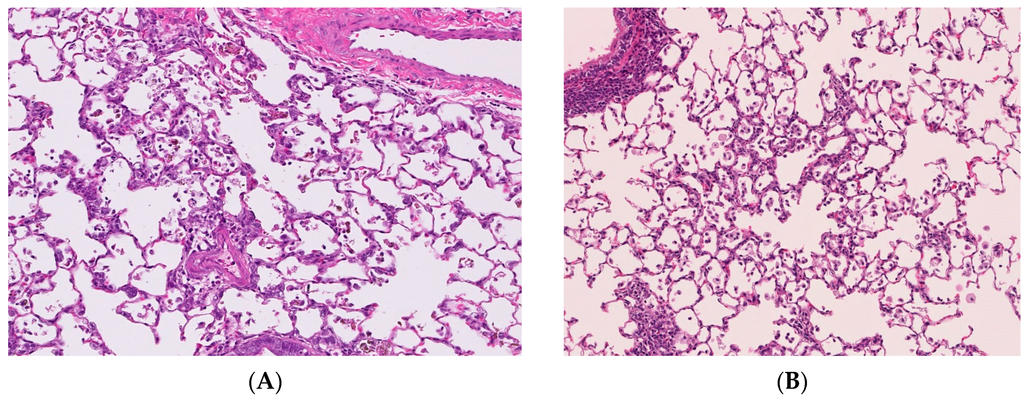

The distribution of the deposition of nanoparticles in the lung following intratracheal instillation is the lesion in which the suspension of nanoparticles is spread, namely the centriloblar spaces, which are the neighboring alveolus lesion around the peripheral respiratory tract (Figure 2A). The infiltration of inflammatory cells such as neutrophils and macrophages with the accumulation of nanoparticles was observed in this centrilobular space after intratracheal instillation [6,20].

On the other hand, there are reports in which the distribution of infiltration of inflammatory cells in the lung was mainly in centrilobular lesions just after the end of the inhalation exposure of nanoparticles [9,21,22,23] (Figure 2B). Although the main lesions in the lung following the inhalation of nanoparticles are centrilobular lesions, as in intratracheal instillations, the inflammatory lesions were observed not only deeply in the alveolar wall but also in the subpleural area [9,22].

Figure 2. Pathological features of lung tissue. Magnification 100×. (A) Lung tissue following intratracheal instillation of NiO nanoparticles; (B) Lung tissue following inhalation of NiO nanoparticles. Distribution of infiltration of inflammatory cells in the lung were mainly centrilobular lesions in both studies.